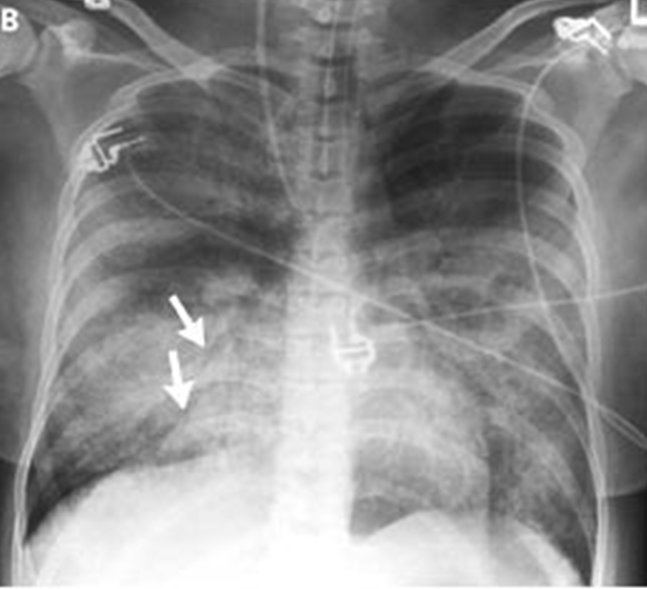

A 51-year-old man who presented with acute anterior myocardial infarction and acute cardiogenic pulmonary edema. Note the enlargement of the peribronchovascular spaces (arrowheads) and the prominent septal lines (Kerley's B lines) (arrows) as well as acinar areas of increased opacity that coalesce into frank consolidations.

interstitial edema causes dyspnea and tachypnea

what is the most likely cause of increased permeability?

C